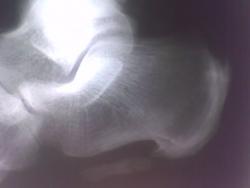

Несколько раз наблюдал переломы остеофитов, причем с соответствующей клиникой, здесь вероятно именно такой случай. Интересно - срастется ли?

Спасибо за комментарии! Я в заключении написал, что выше отметили коллеги: "Оссификация подошвенного апневроза".Цель демонстрации: за 25 лет работы столь выраженные изменения, вижу впервые.Не уверен, что есть перелом оссифицированного апоневроза.

Кстати, у него - же, на мой взгляд, косто-хрящевой экзостоз по тылу таранной кости.